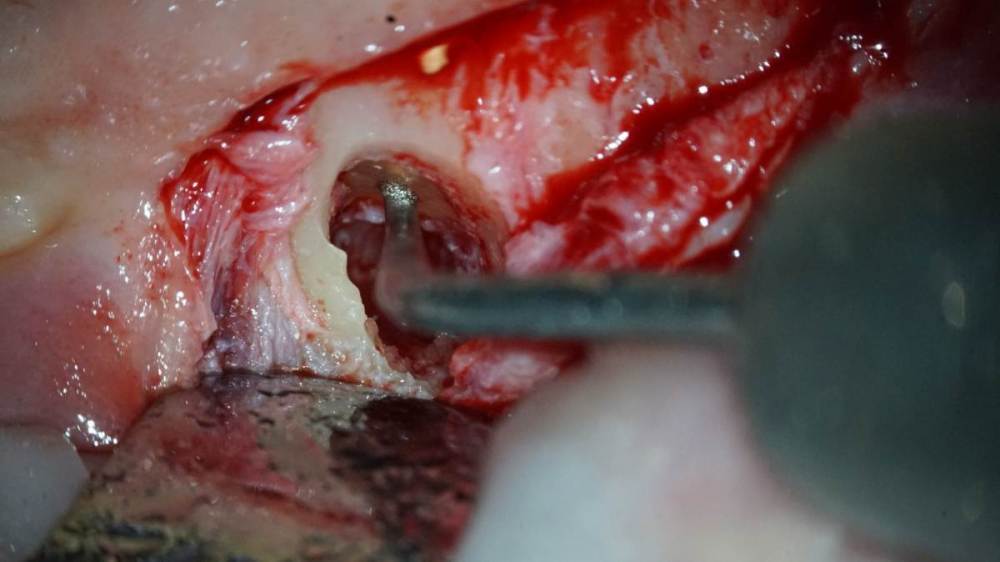

TIGER Опубликовано 1 октября, 2022 Поделиться Опубликовано 1 октября, 2022 Всем хорошего дня!Иногда некачественное эндо может привести к фатальным последствия,тут мы успели принять меры и сохранить и зуб и имплант!Вывод:эндо подготовка зубов прилегающих к зоне имплантации должна проводиться до имплантации!P.s винтик от НКР уже 7 лет там 3 Ссылка на комментарий